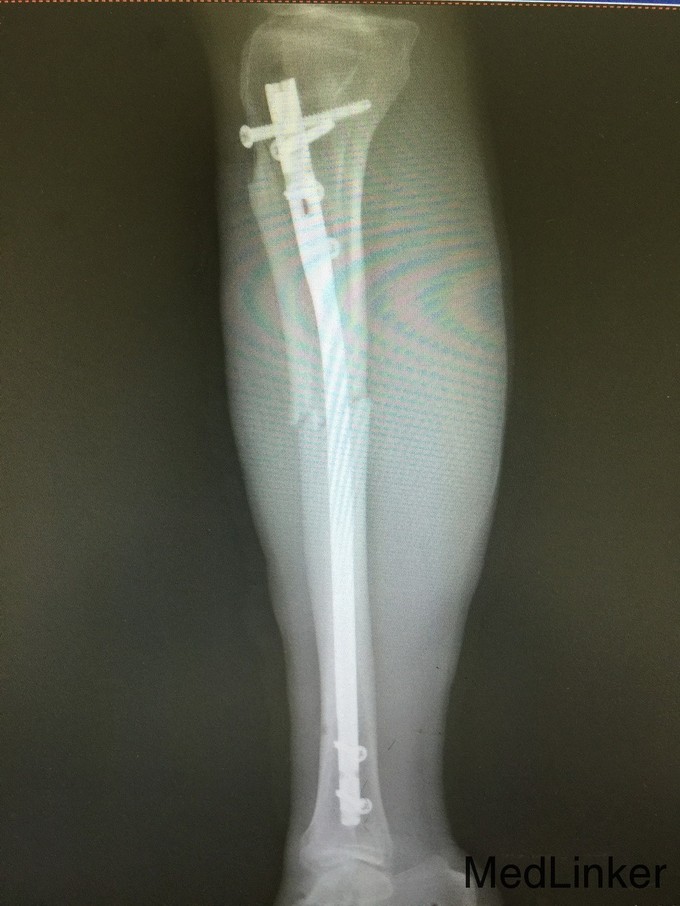

患者,李某,男,59岁。因“右小腿外伤后肿痛伴活动受限1小时”入院。一小时前,患者右小腿被机器轧伤,当即出现疼痛,肿胀,伴活动受限。随即被同事送来我院就诊,门诊行X线检查后,遂以:“右胫腓骨粉碎性骨折”收入院。起病来,饮食睡眠大小便无异常。既往史:无特殊。

右小腿肿胀,畸形,瘀斑,局部压痛及叩痛。足趾血运可,感觉存在。右胫腓骨CT平扫+三维重建:右胫腓骨粉碎性骨折。

诊断:右胫腓骨粉碎性骨折。 入院后完善检查,入院后第九天行闭合复位交锁髓内钉内固定术。